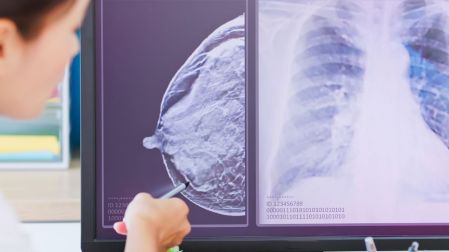

No realizar la primera mamografía eleva la mortalidad por cáncer de mama

Omitir la primera mamografía aumenta hasta 3.6 veces el riesgo de cáncer de mama en etapa avanzada y eleva la mortalidad a largo plazo.

La primera mamografía se considera un paso decisivo: omitirla no solo retrasa el diagnóstico, sino que puede multiplicar el riesgo de enfrentar el cáncer de mama en etapas más avanzadas y con mayor mortalidad.

De acuerdo con una investigación publicada en la revista The BMJ, realizarse la primera mamografía puede marcar una diferencia determinante en la salud de una mujer.

No asistir a esta prueba de detección temprana no solo retrasa el diagnóstico, sino que se asocia con un riesgo mayor de desarrollar cáncer de mama en etapas avanzadas y, en consecuencia, con una mayor probabilidad de morir a causa de la enfermedad.